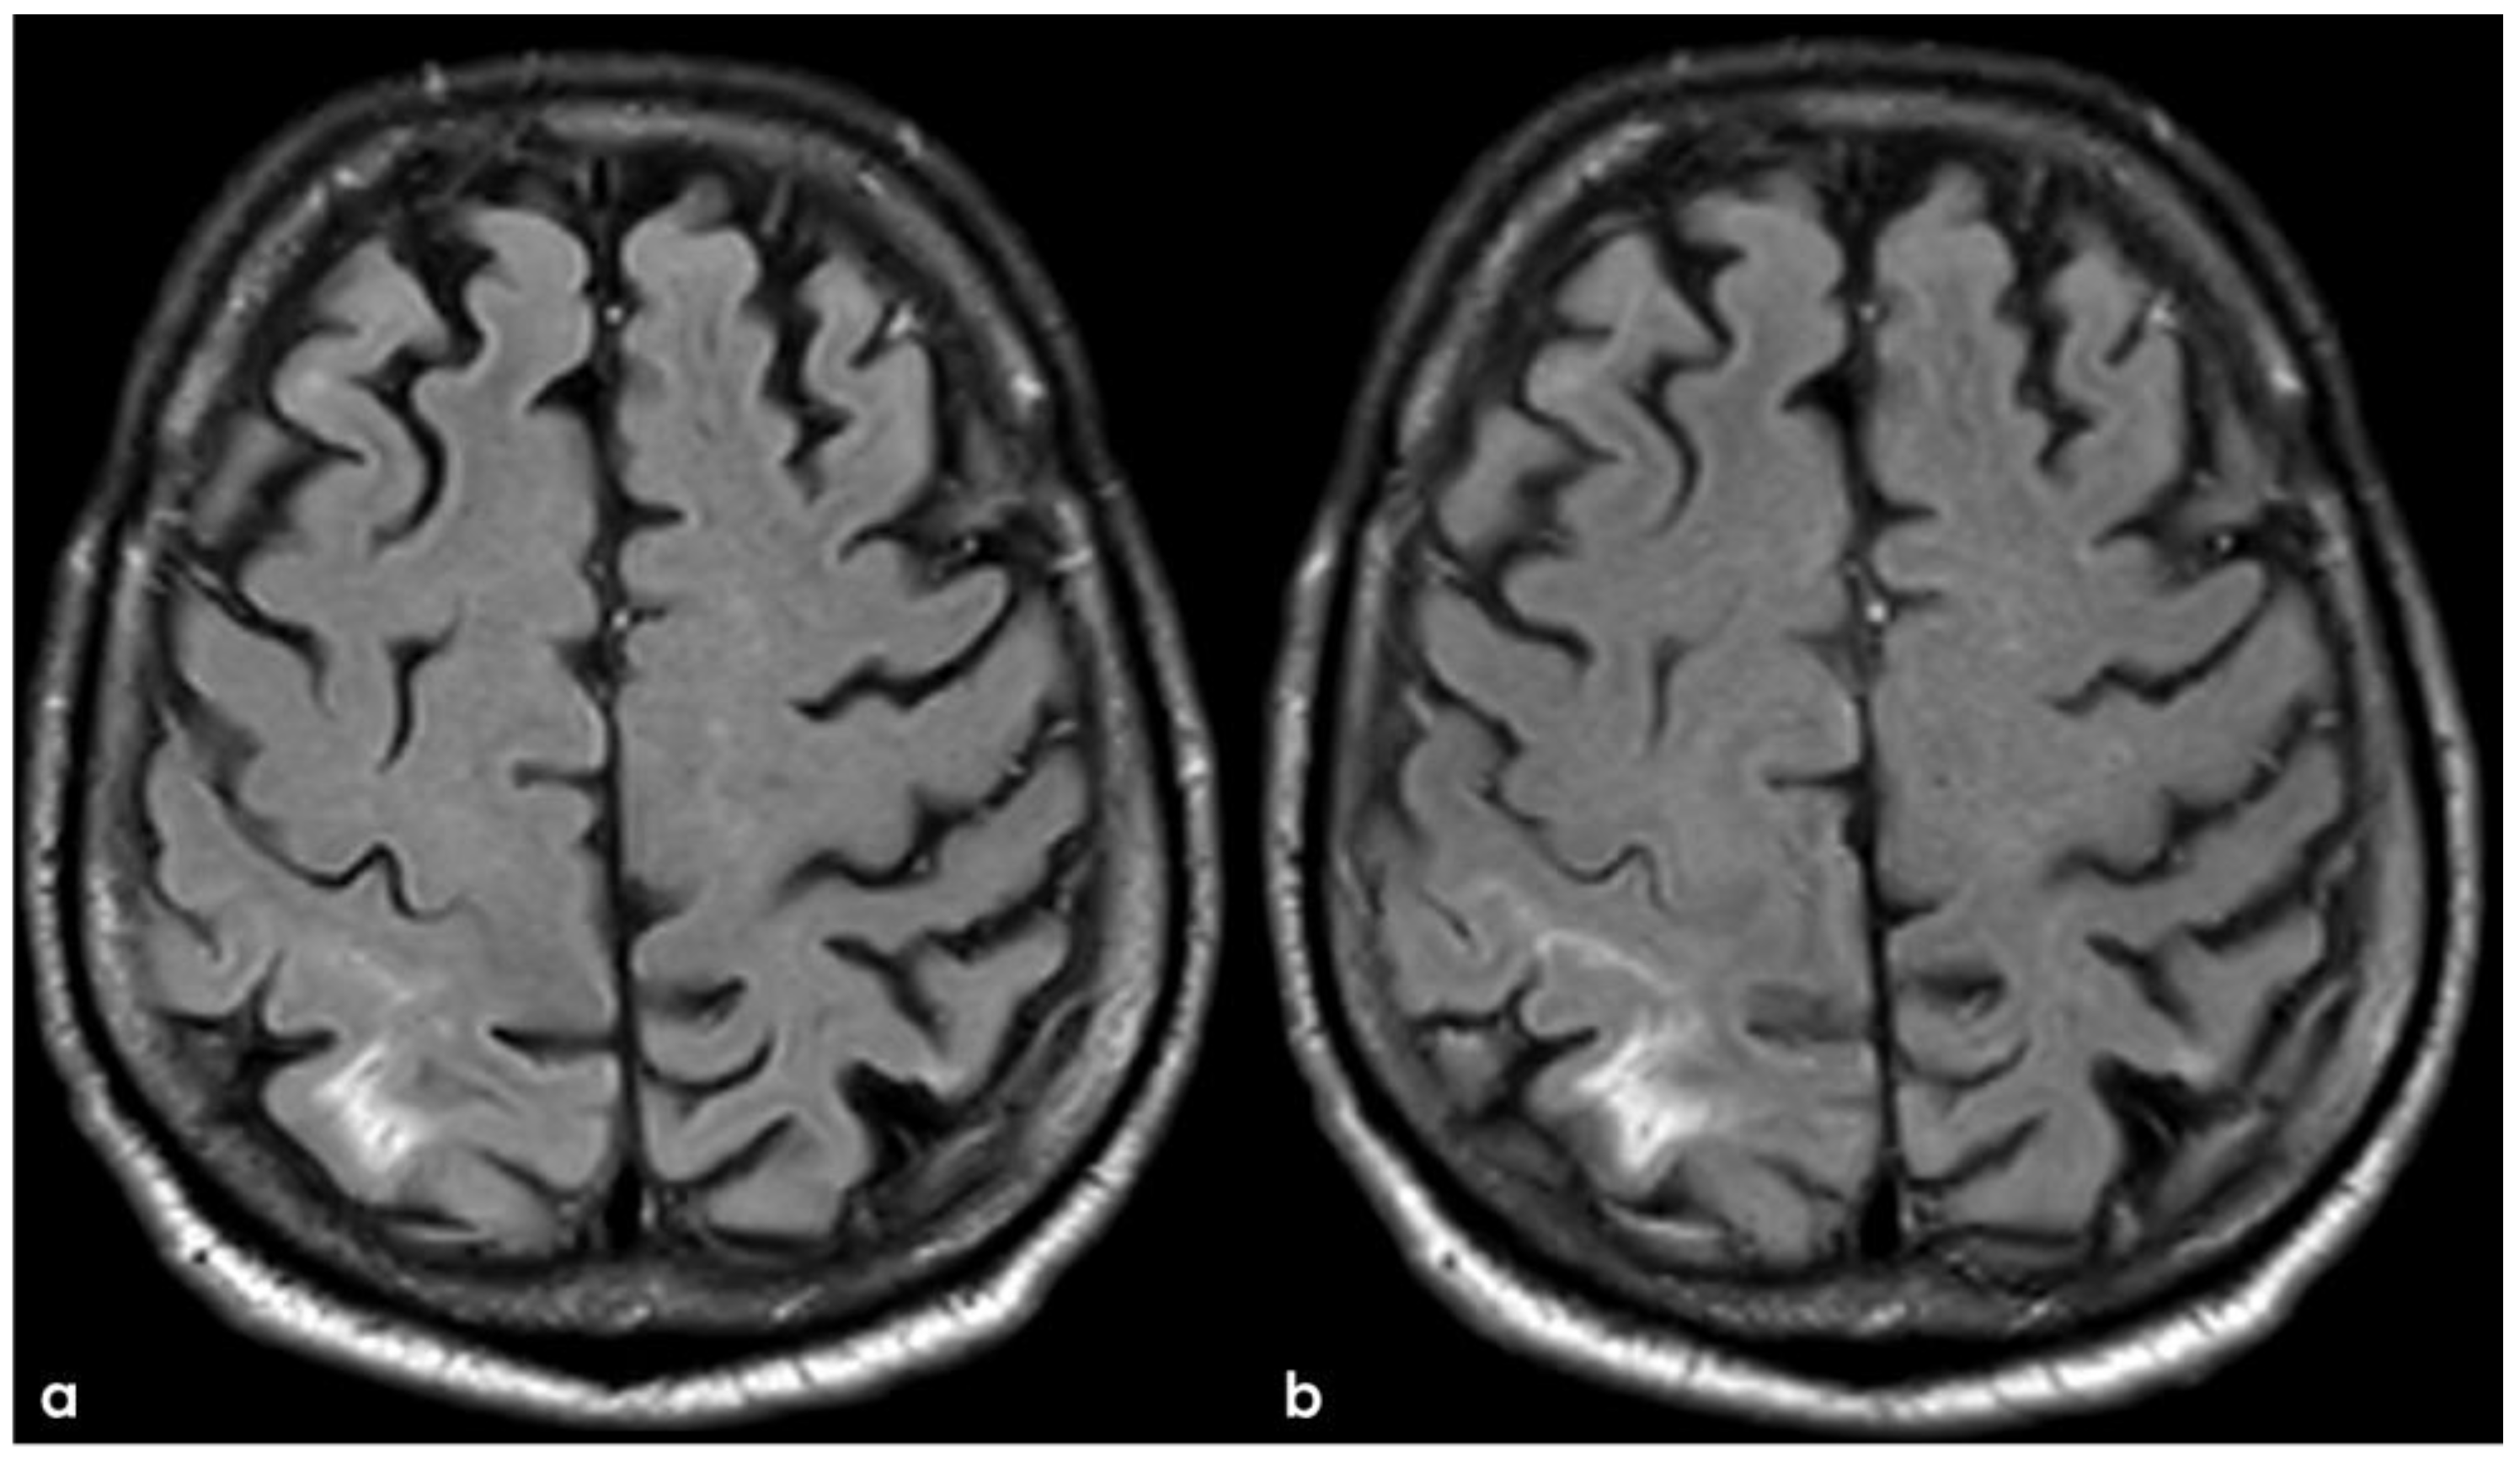

4. December 2015: Ischemic Stroke

5. February 2017: First Recurrent CAA-Related Inflammation